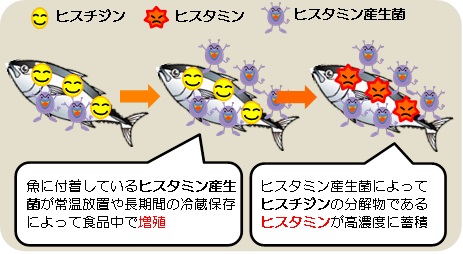

ヒスタミン食中毒は、生魚中で生成された大量のアレルギー反応誘発物質ヒスタミンが原因。ヒスタミンは加熱調理した後でも失活せず、強烈でエピペンが効かないアナフィラキシーを引き起こします(アレルギー様食中毒)。

赤身魚(マグロ、ブリ、サンマ、サバ、イワシ)などのエラや内臓に多く含まれるアミノ酸の一種ヒスチジンが、微生物(ヒスタミン産生菌)の酵素作用でヒスタミンに変化します。赤身魚のエラ・内臓を処理しないまま室温で4-5時間放置すれば、アナフィラキシーを起こすのに十分なヒスタミンが生成されます。ヒスタミンは加熱調理しても分解されません。

また、ヒスタミンはワインやチーズ等の発酵食品にも多く含まれます。

ヒスタミン食中毒の治療は、抗ヒスタミン剤と輸液の対症療法しかありません。

ヒスタミン食中毒の予防は、

- 鮮度が低下した魚を材料にして作られた料理を食べない。例えば、誰かが釣ってきた魚、売れ残った魚で作られた可能性のあるお惣菜。

- ヒスタミンを高濃度に含む食品を口に入れた時、唇や舌先にピリピリした刺激を感じる事があります。決して食べてはなりません。